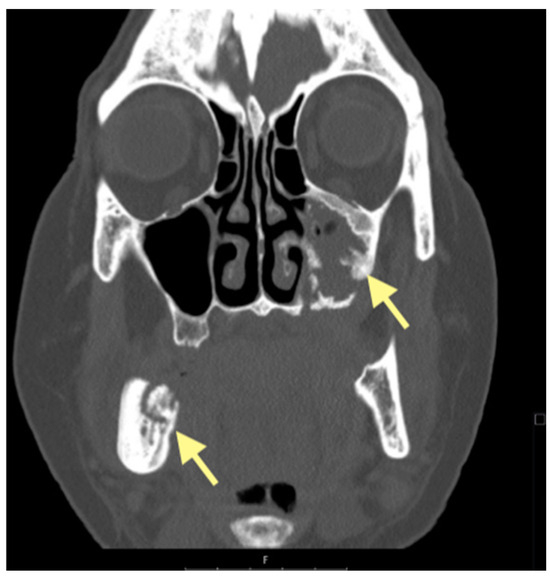

The third patient was a 75-year-old female with osteonecrosis of the mandible and maxilla in the fourth and in the second quadrant (see Figure 7, Figure 8 and Figure 9). The patient had third-stage jaw osteonecrosis. In 2023, the patient was diagnosed with osteonecrosis of the upper and lower jaw caused by antiresorptive therapy (until August 2021, the patient regularly used Zolendronic acid; then, this drug was replaced by the RANKL inhibitor Denosumab). The treatment was periodically complicated by submandibular and submental abscesses. In addition, due to the progression of the underlying disease, constant courses in chemotherapy were administered. The patient underwent three operations, which included sequestrectomy of the jaw with simultaneous use of A-PRF, antrotomy with revision of the maxillary sinus, closure of the oroantral communication, and opening and revision of abscesses of the soft tissues (see Figure 10 and Figure 11)

Figure 7.

CT of the head and facial bones (16 December 2024).

Figure 8.

Figure 9.